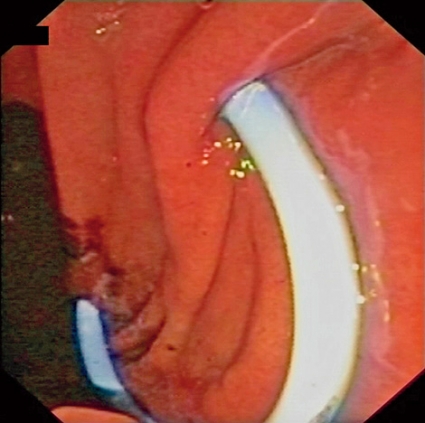

Terapeutiska indikationer

De terapeutiska möjligheterna med endoskopiskt ultraljud expanderar kontinuerligt. I nuläget är det vanligt att man använder metoden för dränage av pseudocystor i pankreas [19] (Figur 12). Andra terapeutiska indikationer inkluderar coeliacus-blockad och neurolys på grund av av smärtor vid kronisk pankreatit och pankreascancer. Dessutom utvecklas nya terapeutiska områden inom ramarna för kliniska studier, t ex dränage av obstruerade gallvägar, lokal injektion av läkemedel, etanolablation av cystor och tumörer, anläggande av intrahepatisk portosystemisk shunt och som hjälpmedel för säker NOTES (natural orifice transluminal endoscopic surgery).